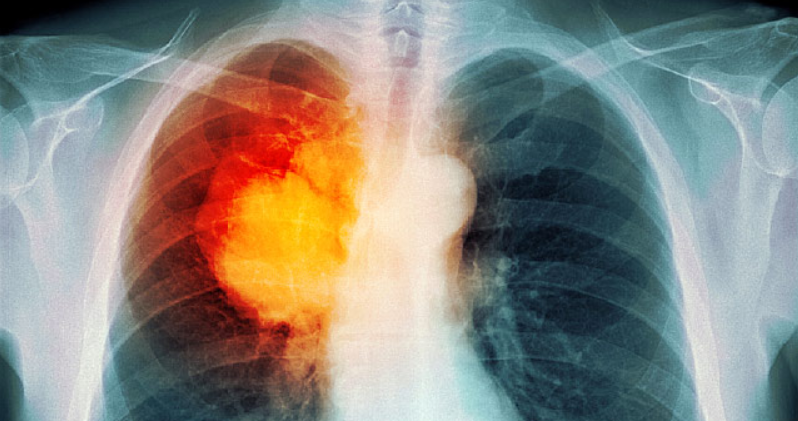

폐암과 관련된 허리 통증의 증상은 다양하며 다른 상태로 인한 허리 통증과 크게 겹칩니다. 그것이 척추와 관련된 경우, 그것은 등 부상의 많은 증상을 모방 수 있습니다.

폐암과 관련된 허리 통증은 근육 통증이나 날카로운 신경처럼 날카로운 것과 같이 일반화될 수 있습니다. 부신 동반 질환이 있는 사람들은 때때로 자신의 등 쪽에 있는 "신장 통증"에 대해 불평하거나 "신장에 구멍을 뚫은"느낌을 묘사할 수 있습니다.

즉, 폐암과 관련된 허리 통증에는 특정 징후가 있을 수 있습니다. 허리 통증은 폐암으로 인한 것일 수 있는 사항은 다음과 같습니다.

휴식을 취하는 허리 통증

야간 최악의 허리 통증

어떤 활동 없이 발생하는 허리 통증

침대에서 더 오랫동안 누워있을 때 아픈 통증

심호흡을 할 때 더 심해지는 등 통증

물리치료 나 다른 의학적 개입에 반응하지 않는 허리 통증

또한 지속적인 기침, 호흡 곤란, 의도하지 않은 체중 감소, 만성 피로 또는 기침과 같은 기타 징후가 동반된 요통은 폐암의 가능성을 뒷받침할 수 있습니다. 척추 골절과 관련된 허리 통증은 의사가 폐암에 대해 생각하게 해야 합니다.